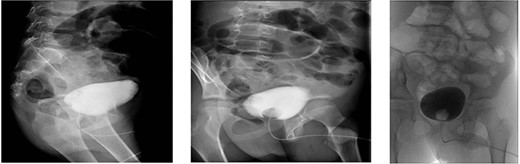

A CT cystography was performed, and it showed a vesicourachal diverticulum. The suprapubic drain that was placed intraoperatively was shown to be penetrating the diverticulum (Fig. 2). The urology department was consulted and the patient’s condition was discussed with his family. Management options were offered, including conservative management with Foley catheter placement and operative repair; the family opted for conservative management. The management included hourly monitoring of his urine output, antibiotic prophylaxis with intravenous cefuroxime 625 mg thrice a day and intravenous metronidazole 350 mg thrice a day, daily laboratory investigations (complete blood count, renal function tests and serum electrolytes), and a cystography performed after 7 days. The patient’s daily urine output is shown in Table1.

Multiple sagittal views showing the drain penetrating the urachus.

A contrast cystogram was performed on postoperative day 9, and a pelvic scan showed no leak or extravasation of the contrast fluid (Fig. 3). The catheter was removed, and the patient was discharged after successful micturition trials. Follow-up examinations performed 2 weeks and 1 month post-discharge were unremarkable and the patient presented no complaints.

Cystogram performed on postoperative day 8 showed no extravasation of the contrast material.